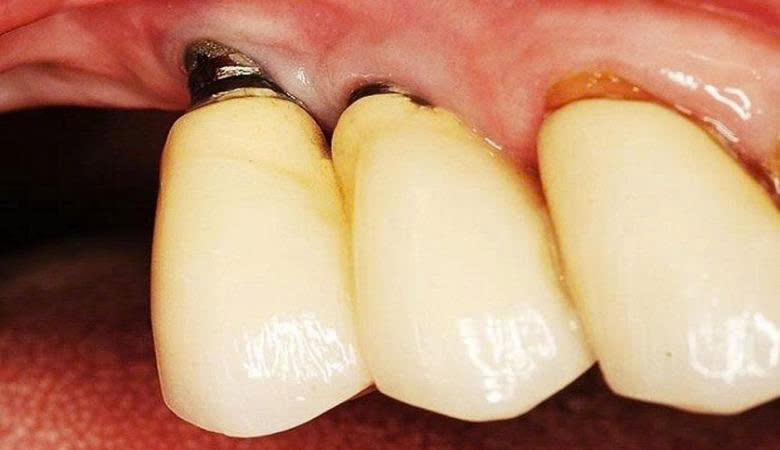

5. Kích ứng, dị ứng do trụ kém chất lượng

Trụ implant không đạt tiêu chuẩn có thể gây kích ứng trong khoang miệng (Nguồn: Internet)

Titanium nguyên chất là vật liệu tiêu chuẩn, tương thích sinh học tốt. Trụ giá rẻ có thể pha tạp chất (niken, chì, kẽm), gây dị ứng, viêm nướu, sưng, đau và thậm chí đào thải trụ.